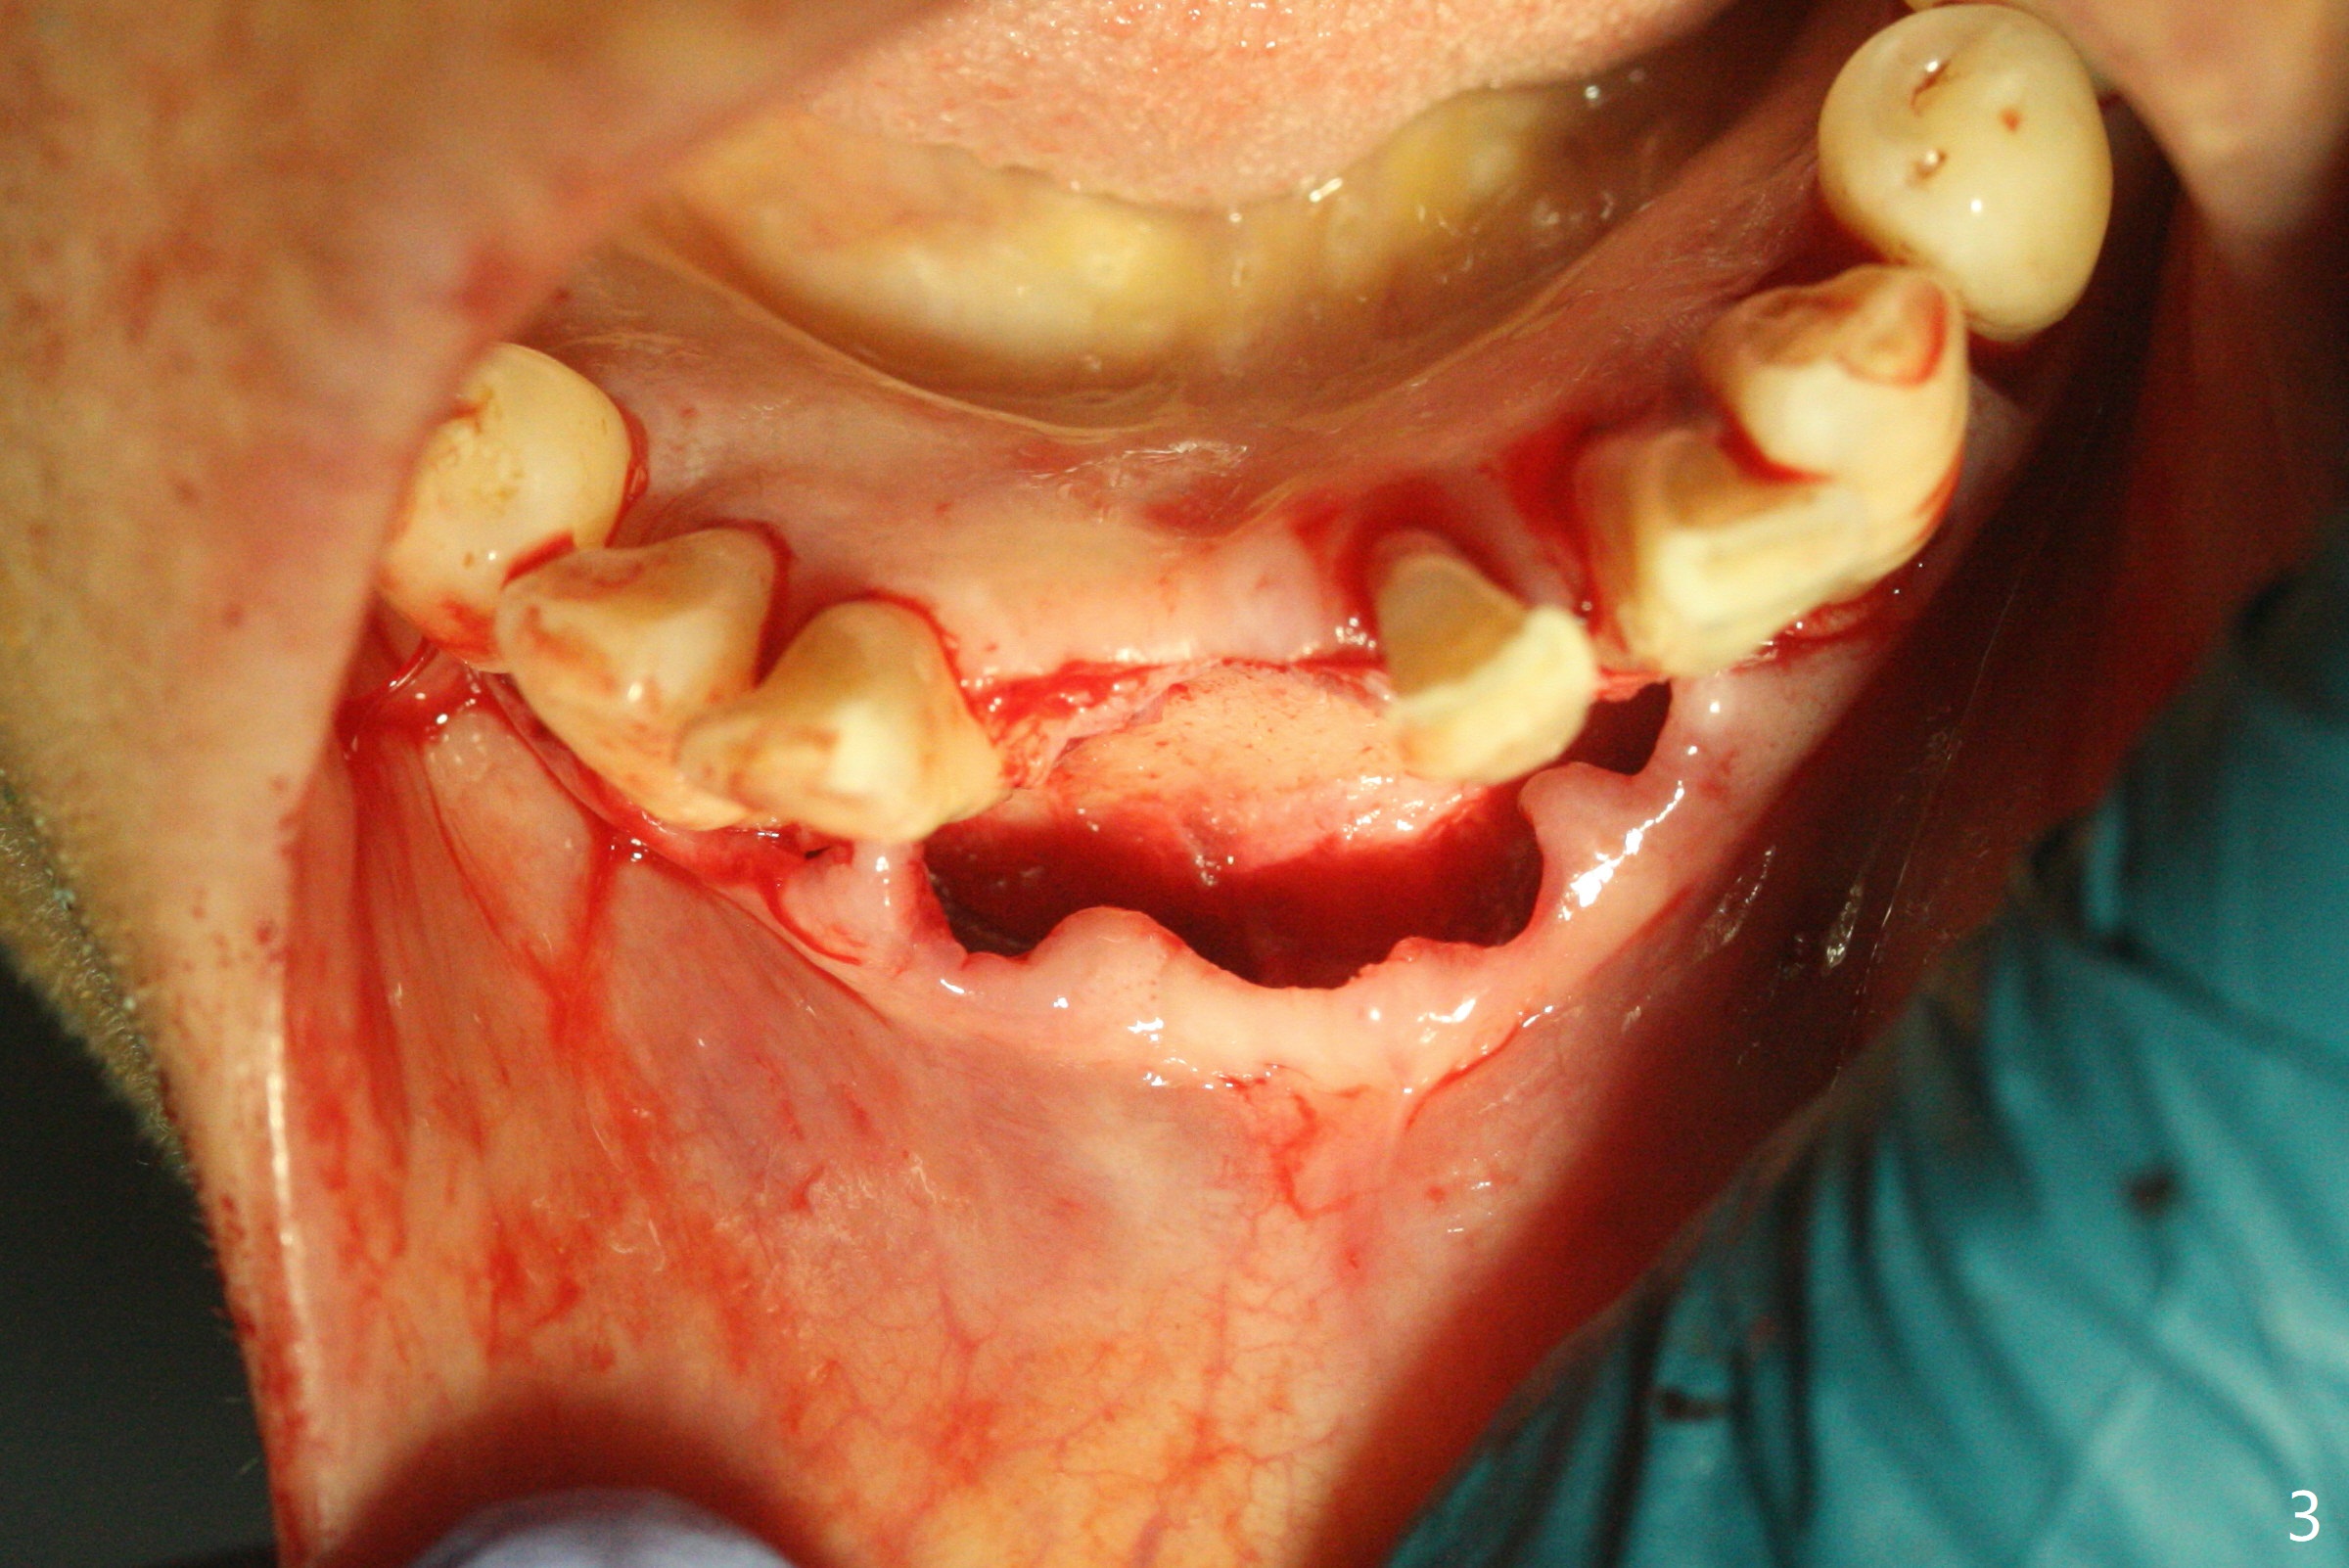

56岁女十分恐惧治疗,缺失右下1,其余切牙由于骨质吸收颊侧移位(图一:1,2),但是她不愿意拔除,同意右下1种植,牙周骨手术,植骨;植体整合后作为支抗,矫正移位下门牙。为了防止忘记舌侧瓣分离,先做舌侧切口(图二),然后颊侧瓣松弛分离(图三),包括使用前牙隧道刀(图四)切断颊侧骨膜,松弛到颊侧瓣能向舌侧牵拉3-4毫米(图五),舌侧瓣骨膜下广泛,深部分离(好像不能切断骨膜,图六),放置导板,磨平狭窄的牙槽嵴(图七:O(osteotomy)),植入2.5x12(4)毫米一段式植体(图八:故意舌侧植入,以便以后矫正),在颊侧骨板打多个出血洞(图八:箭头),然后把在平的器皿上形成的粘性骨板(sticky bone,图九),放置于植体和移位切牙周围(图十),接着使用消毒过的橡皮障punch(图十一(纸头相当于PRF膜;事先给助手示范))在三个PRF膜(图十二)打洞,套在植体和门牙上(图十三: 箭头),防止膜(图十四)和骨块(图十五,十六:*)移位,最后还必须使用最原始方法牙周敷料保护伤口(图十七)。术后9天,舌侧牙周敷料脱落,伤口稍微裂开(图十八)。术后18天撤除敷料,伤口裂开处有新鲜肉芽组织生长(图十九(*:下面是填入的骨粉,将是增宽的牙槽嵴(如果你是乐观主义者)),二十)。病人十分感激我们帮助她度过难关。她的确有sleep apnea,否定tongue thrust。术后三个月植体周围没有明显骨质吸收(图二十一至二十三),左下1,2轻度反合(图二十四),植体周围软组织健康(图二十五),5-5安置矫正器(图二十六,二十七,12 niti)。一周后下切牙向舌侧移动(图二十八),左下1,2反合纠正(图二十九)。再一周变化不大(图三十),植牙圈有些松动,两周后将重做临时牙冠,槽往舌侧移动。结果病人提前回来,植牙槽舌侧移位。一周后右下2不适(图三十一),尝试近中牵引(图三十二)。